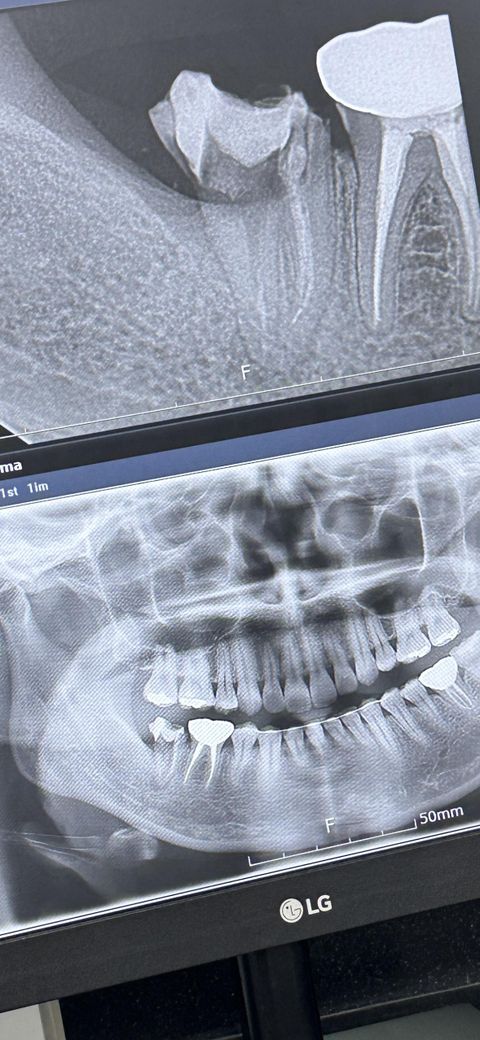

3-4군데 치과 모두 맨끝 어금니를 발치 해야된다고 해서 임플란트 하려고 합니다

제 나이는 35이고 뿌리끝 염증이 있습니다

사진보시면 ㅠ 뼈이식이 필요할까요?

사진으로 봤을 경우에는 치조골의 형태가 매우 온전하게 보존되어 있는 것으로 보입니다. 굳이 고리식을 하지 않아도 될 것으로 생각되지만 정확한 확인을 위해서는 CT 사진 등이 필요할 수 있습니다

저정도면 기다렷다가 잇몸뼈가 차고 나서 임플란트를 하셔도 될것같습니다. 염증이 심한거 같진 않아 보입니다.

우선은 발치후에 잇몸 뼈가 채워지는 상황이 확인이 되어야 뼈이식 필요여부가 결정이 됩니다. 따라서 3개월정도 지켜보고, 만약 채워지는 정도가 너무 늦고 주변치아가 이동하는 경우에는 뼈이식후 임플란트 진행을 권합니다.